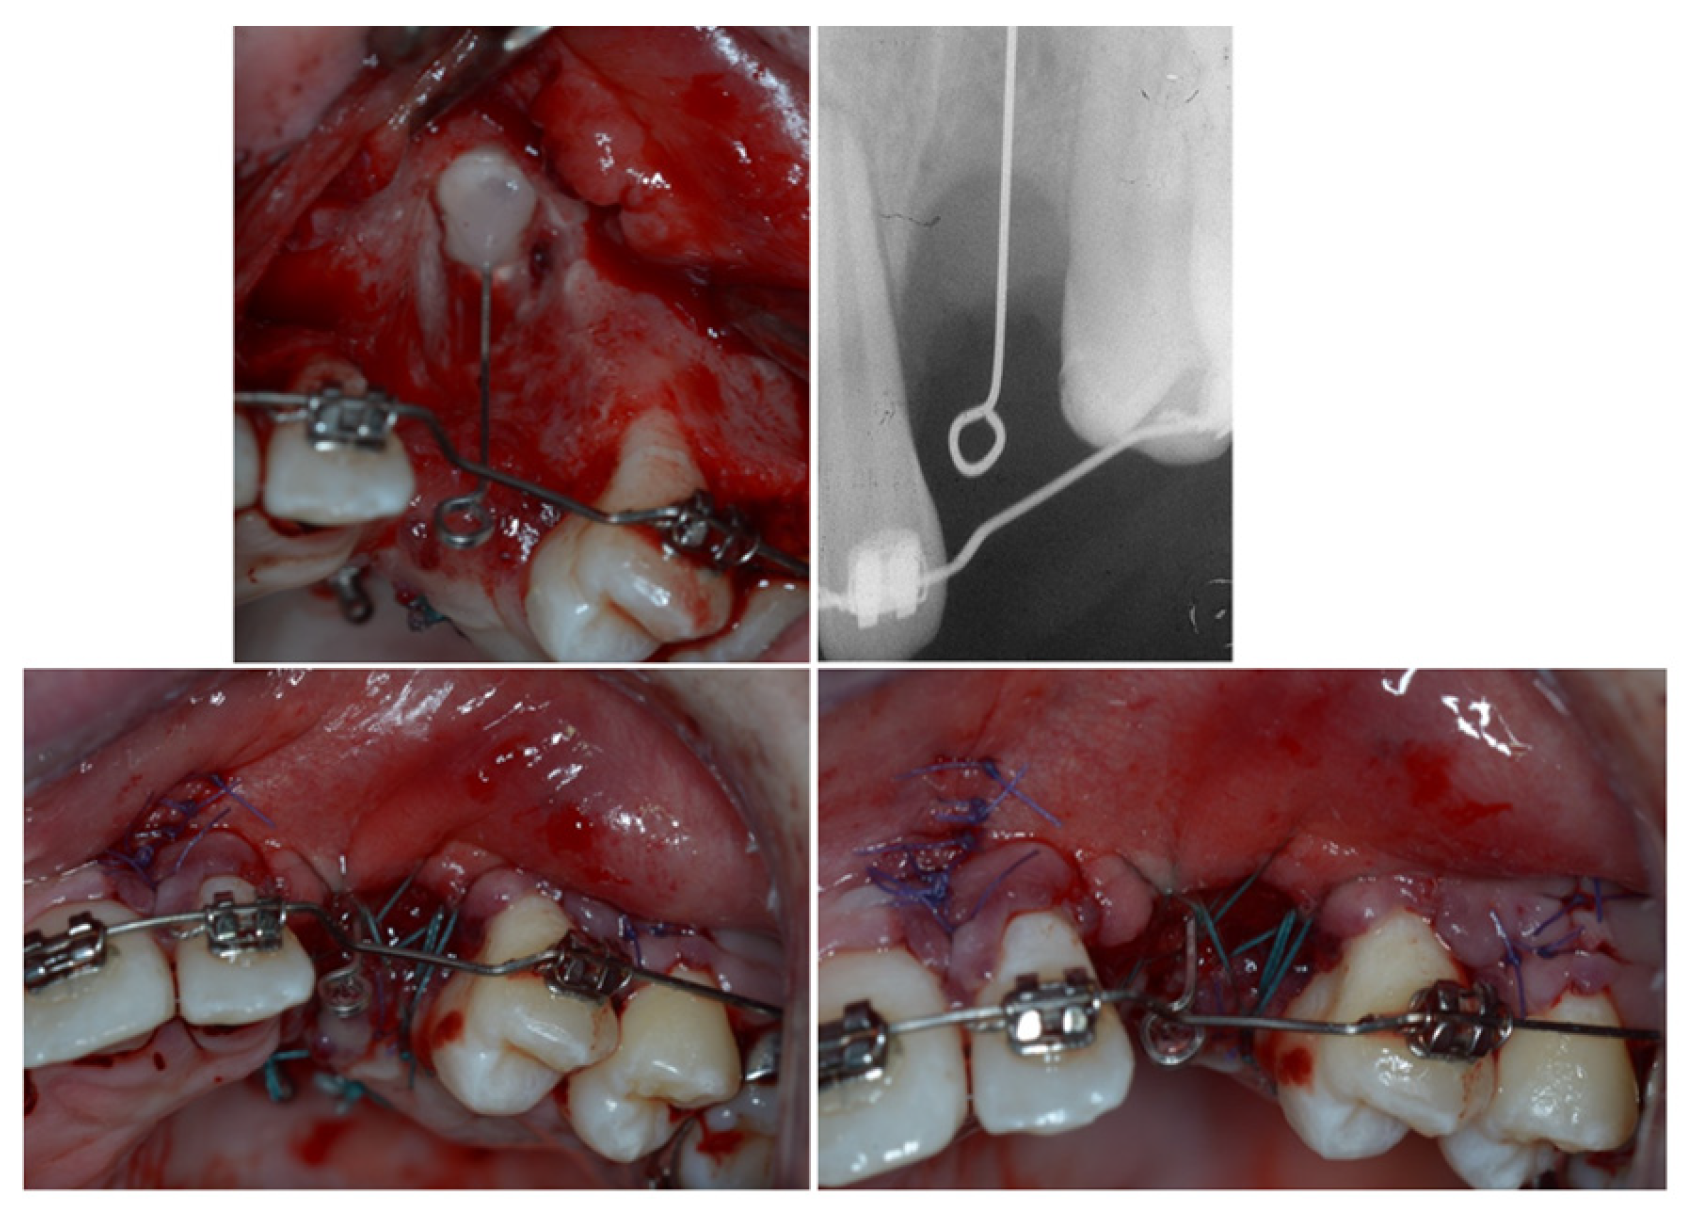

3. Therapeutic Interventions